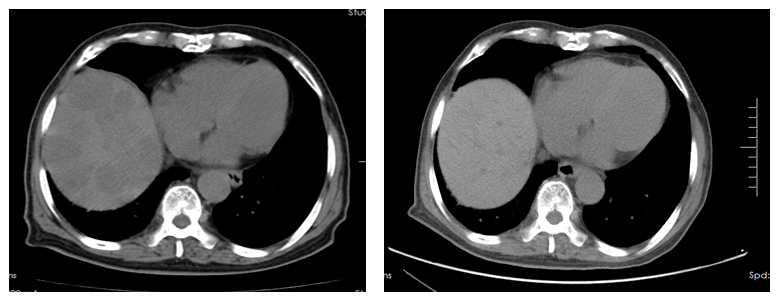

2024年3月10日行胸部+腹部CT:胃癌术后改变,残胃充盈差,壁增厚,肠系膜内多发小淋巴结,肝内多发转移灶,左肺下叶内前内基底段磨玻璃结节(图3)。

17.5.png

图3. 腹部CT检查(2024年3月10日)

目前诊断:胃恶性肿瘤伴肝内多发转移[rT4aN2M1 IVB期 HER2(2+)FISH(-) pMMR]